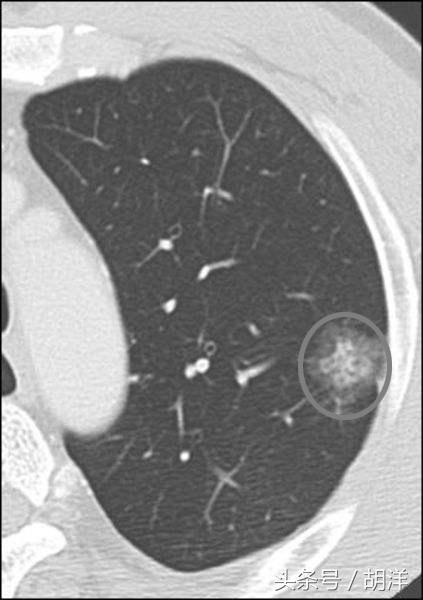

肺部发现内实外虚的小肿块

肿瘤的生长一般是一个点或者多个点先恶变然后向外生长,因此早期肺癌一般中间密度高,周围密度略低,或者说中间是点状的密实影子,周围是磨玻璃影,这种情况要当心,周围磨玻璃影越大,越有可能是恶性。